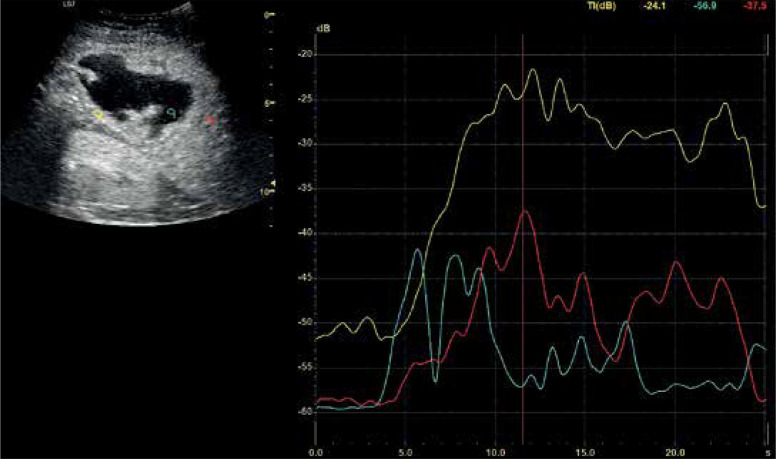

Results: The contrast enhancement pattern on CEUS matched post-contrast CT. Lesion size detected by CEUS ranged from 1.16 cm to 15.33 cm (median 5.74 cm). CT classified lesions into four types: I (tumor-like) - 2, II (honeycomb) - 5, III (lacunar) - 23, IV (cystic-like) - 34. CEUS fully agreed with these classifications. B-mode missed two type I lesions. For type III abscesses, agreement with CEUS was perfect (κ = 1, 100%), and moderate with B-mode (κ = 0.50, 79.7%). For type IV abscesses, agreement with CEUS was perfect (κ = 1, 100%), and high with B-mode (κ = 0.88, 93.75%). Pus enhancement remained stable (± 15 dB), while the abscess pouch background varied (± 11 dB to ± 6 dB). The Mann-Whitney U test confirmed these observations (arterial: p = 1.02e-14, portal: p = 3.79e-12, late venous: p = 4.53e-13). No significant difference in enhancement values was found based on abscess size (> 4 cm vs. < 4 cm).